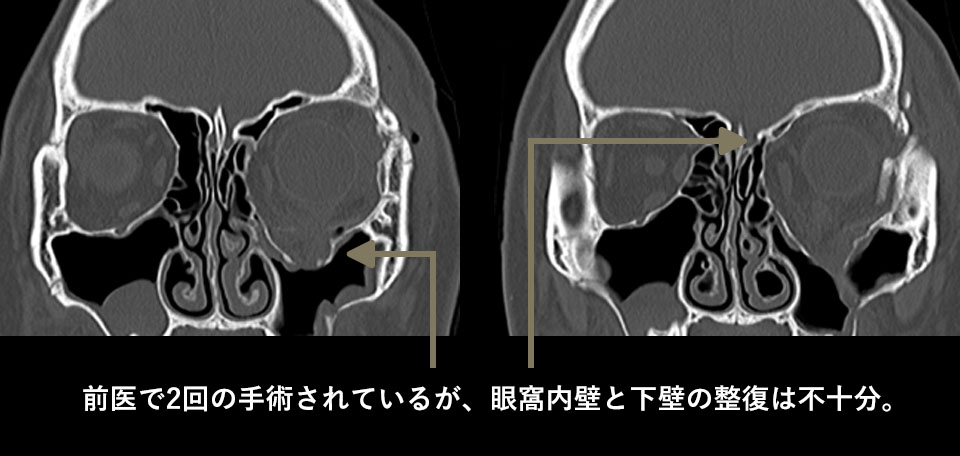

CTでは再建手術を2回されているものの、骨壁を治すことが出来ていないため、眼窩の断面積が縮小していません。これが眼球陥凹の大きな原因でした。